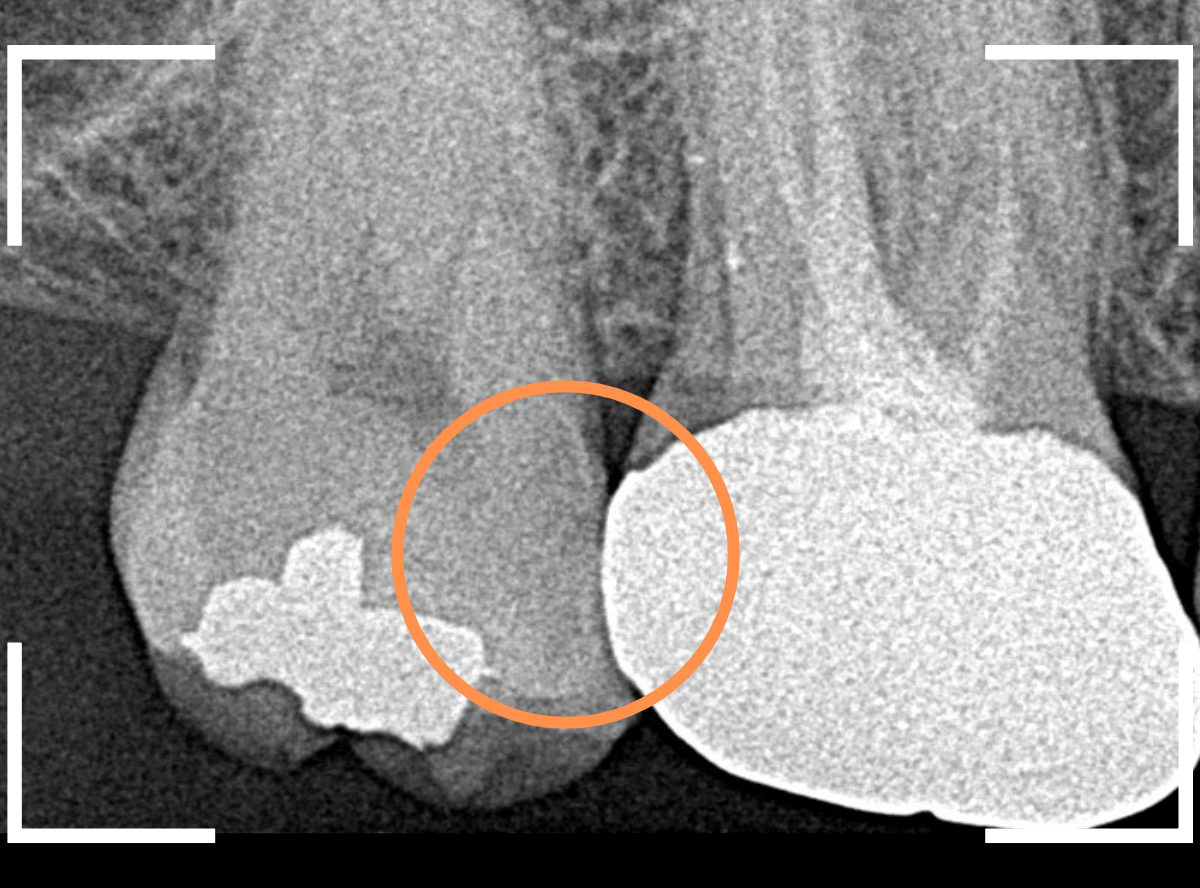

Case.22 痛みはないけど、歯のすきまから大きな虫歯

上の小臼歯の間が虫歯になっていた患者さんです。

症状はありませんし、見た目からも虫歯があるかはわかりませんでした。

レントゲン写真で確認します。

赤い線が虫歯、青い線が歯の神経です。

歯のすきまから両側に虫歯が大きく広がっているのが確認できます。

治療を開始します。

少し削ると、中からすぐに虫歯が出てきました。

ある程度、虫歯を除去したところで、う蝕検知液で確認します。

赤く染まっている部分が虫歯です。

まだまだ虫歯が中で残っている状況で、かなり深い虫歯なのが確認できます。

全ての虫歯を除去しました。

レントゲン写真からある程度確認出来ましたが、歯の神経スレスレまで虫歯が進行していました。

ここまで虫歯が進行していても、全く症状を感じない事も多いです。

そして、ある時急に痛みを感じるのです。

虫歯は急に進行しません。

治療後の定期検診で確実に食い止めましょう。